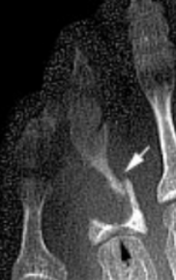

What disease is this? What is shown by A, B and C? | Psoriatic arthritis. A = destructive changes B = Pencil in cup deformity C = IPJ fusion |

What disease is this? What does the arrow show? | Non-articular psoriatic arthritis Arrow = 'fluffy spur' |